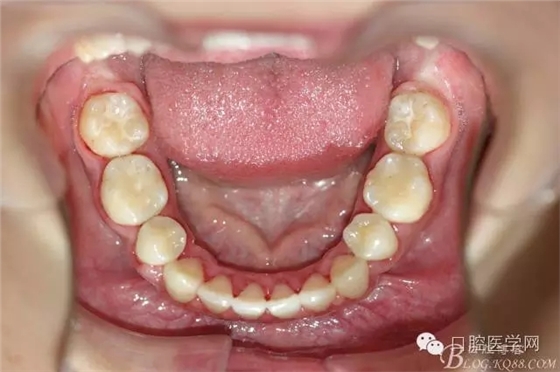

正畸查:替牙合。第一恒磨牙中性合。上牙弓尖圓型下牙弓方圓型。前牙覆合3度覆蓋7.5mm。下前牙咬到上舌側(cè)牙齦。上頜擁擠4.0mm,下頜擁擠

3.0mm。上頜稍前突下頜后縮,上下唇前突,上前牙覆蓋下唇,下唇外翻。面下三分之一過短,頦唇溝明顯,開唇露齒,頦饜窩明顯。顳下頜關(guān)節(jié)開閉口無彈響,無壓痛,開口型開口度正常。

2:拔牙矯治,拔出4顆第一前磨牙。

3:上下頜利用拔牙間隙解除擁擠并內(nèi)收上下前牙,改善唇側(cè)貌。

4:導(dǎo)下頜向前改善頜面?zhèn)让病?p style="text-indent: 2em; text-align: left;">5:上頜TPA+NanceArch強(qiáng)支抗.